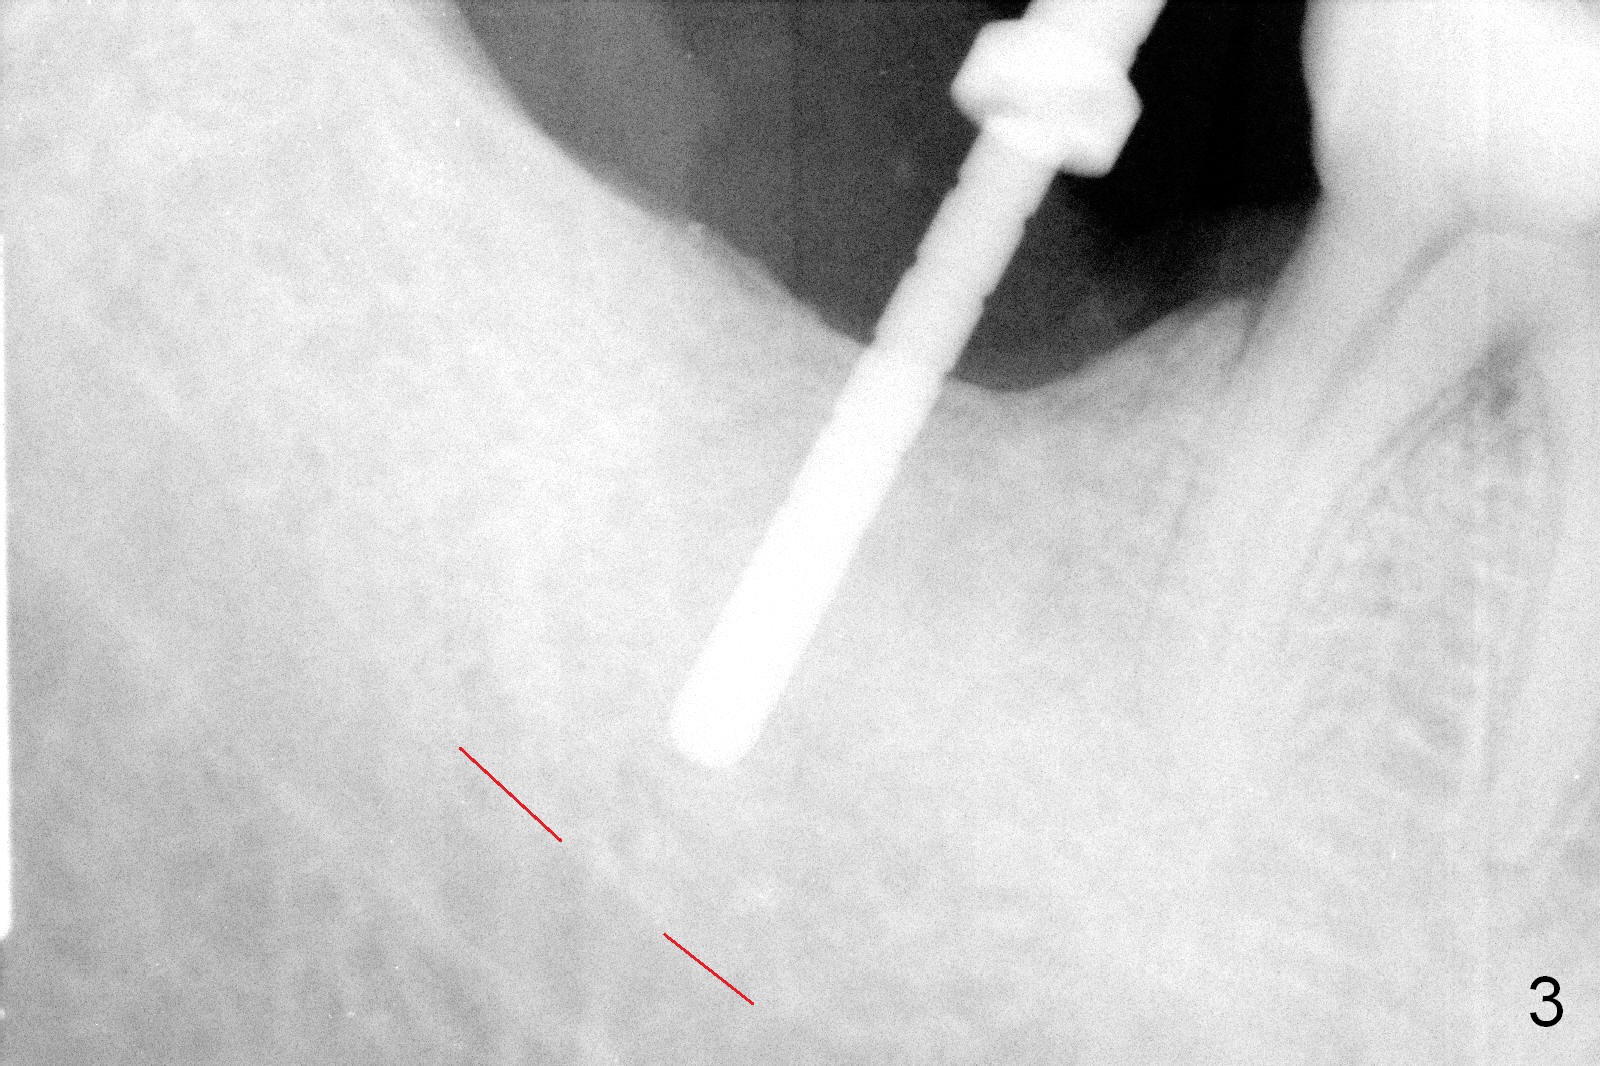

The 61-year-old man is nervous about dentistry. When he returns for #4 implant, he wants an implant at #31 first. Fig.1 shows #31 crown fracture after root canal therapy. Three years after crown placement, there is sign of mesial root fracture (Fig.2 arrowheads). Four years post extraction, bone height is 12 mm (Fig.3 parallel pin 10 mm). An extra wide implant is to be placed, since there is enough bone width. With infiltration anesthesia, the patient feels pain when a 5.4x10 mm drill is being used, 1 mm short of the desirable depth (Fig.4). After Inferior Alveolar Nerve block, the last drill reaches the depth. A 5.9x10 mm implant is placed with insertion torque 50 Ncm (Fig.5 I). A 7.8x4(3) mm cemented abutment (A) is placed immediately. After suturing, the restorative portion of the abutment is covered by the gingiva. It is probably due to over tightening the sutures. It would be ideal to adjust the gingival level before tightening the second suture.